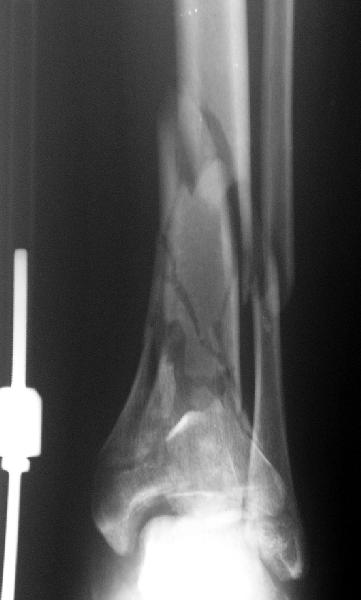

Мне кажется, что все дискутирующие согласным с одним - надо воостанавливать в данной ситуации суставную поверхность. Сделать это закрыто (когда суставная поверхность состит из 3-фрагментов)лично для меня не реально. Конечно можно открыто отрепонировать, зафиксировать спицами и оставить в аппарате, но роль аппарата и выполняет LSP. Разрез в области внутренней поверхность голеностопного сустава и небольшой разрез в ср/3 голени для проксимальных винтов, надкостница не обдирается, пластина вводится подкожно.

Вид конечности на следующий день после операции.

Наверно не дошел, вот еще раз.

8.jpg

14KB (14977 bytes)